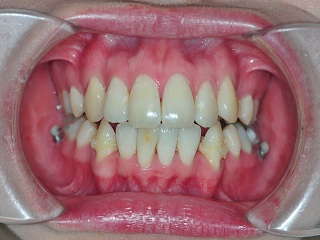

치아교정을 시작하고 나날이 갈수록 치아의 이동이 눈에 확인이 되니깐 신기할 따름이예요~

근데 제 치아이동이 너무 빠르다고 선생님께서 그러시더라구요

순간 아싸>< 했는데, 선생님께서 이동이 너무 빨라도 좋은건 아니라구 하셨어요